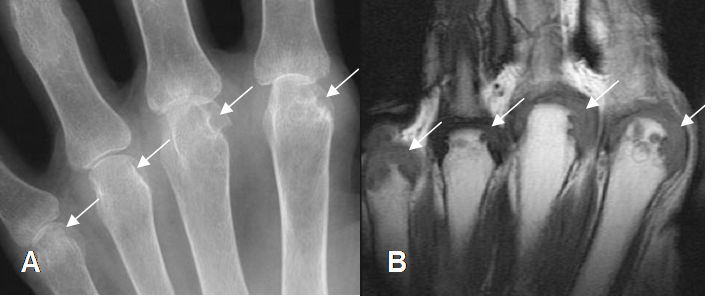

A: Rx AP. Signos de osteopenia y erosión en las cabezas de los metacarpianos.

B: RM coronal en T1. Además de las erosiones en los metacarpianos, hay formación de pannus.